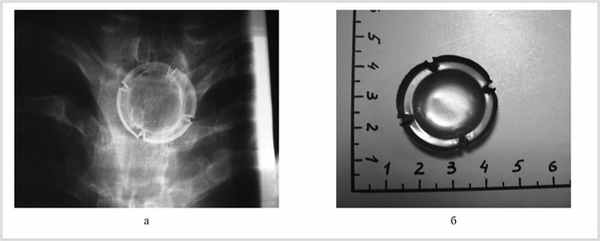

Больной Д., 17 лет, житель Железногорска, поступил в ЛОР-отделение 15.02.12. Жалоб не предъявлял. 13.02 во время прохождения комиссии в военкомате ему была назначена рентгенография органов грудной клетки, на которой было обнаружено инородное тело в верхнем отделе пищевода (рис. 1, а).

Рис. 1. Рентгенограмма органов грудной клетки больного Д. (а), инородное тело пищевода (б).

Поскольку инородное тело являлось металлической пластинкой, которой фиксируется пробка шампанского, больной вспомнил, что во время встречи 2011 г. в тот момент, когда он пил кока-колу из стакана, почувствовал кратковременную боль при глотании за грудиной, на которую не обратил внимания; за медицинской помощью не обращался. В последующие месяцы дискомфорта и болей при приеме пищи не отмечал.

С учетом данных рентгенографии 14.02.12 под интубационным наркозом была выполнена фиброэзофагоскопия, однако инородного тела при этом исследовании обнаружить не удалось. Далее была произведена ригидная эзофагоскопия трубкой № 5. Сразу же за входом в пищевод с большим трудом после плотного прижатия тубуса эндоскопа к задней стенке пищевода удалось увидеть край инородного тела, вогнутой поверхностью обращенного кзади, которое было захвачено щипцами. От попытки извлечь инородное тело вместе с трубкой эзофагоскопа пришлось отказаться в связи с тем, что оно было плотно фиксировано к задней стенке пищевода, возникала опасность его разрыва. Однако при движении вниз инородное тело легко отделилось от стенки пищевода, под контролем эзофагоскопа было смещено в желудок, откуда извлечено после выполнения фиброгастроскопии (см. рис. 1, б). Выполнена контрастная рентгенография пищевода, затеков контрастного вещества в клетчатку средостения нет. На следующий день больной выписан домой в удовлетворительном состоянии. Через месяц произведена фиброэзофагоскопия — патологических изменений в пищеводе не выявлено.

Таким образом, металлическая пластинка находилась в пищеводе более года, не проявляясь какой-либо клинической симптоматикой.